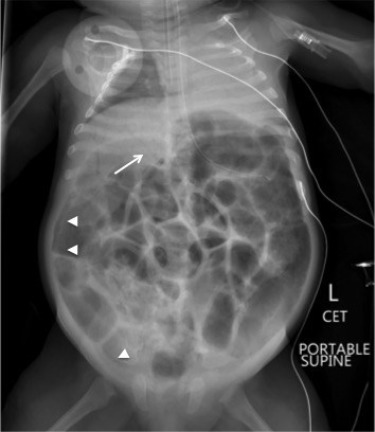

Chẩn đoán Necrotizing Enterocolitis hay Viêm ruột hoại tử là Hỏi bệnh sử và khám thực thể. Chụp X-quang bụng và các nghiên cứu trong phòng thí nghiệm sẽ được thực hiện. Xét nghiệm máu toàn bộ (CBC), xét nghiệm bảng chuyển hóa toàn diện (CMP), cấy máu sẽ được tiến hành để kiểm tra nhiễm trùng và mất cân bằng điện giải.